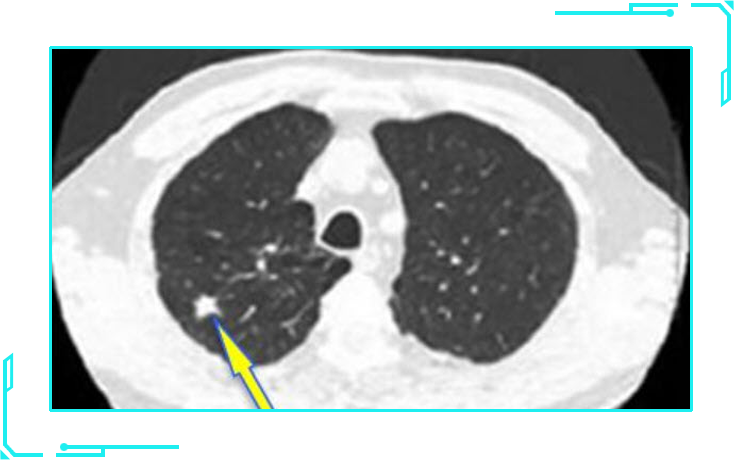

部分实性磨玻璃结节

部分实性磨玻璃结节就如同一个荷包蛋,磨玻璃成分类似其中的蛋清,而实性且密度较高的部分则类似蛋黄。